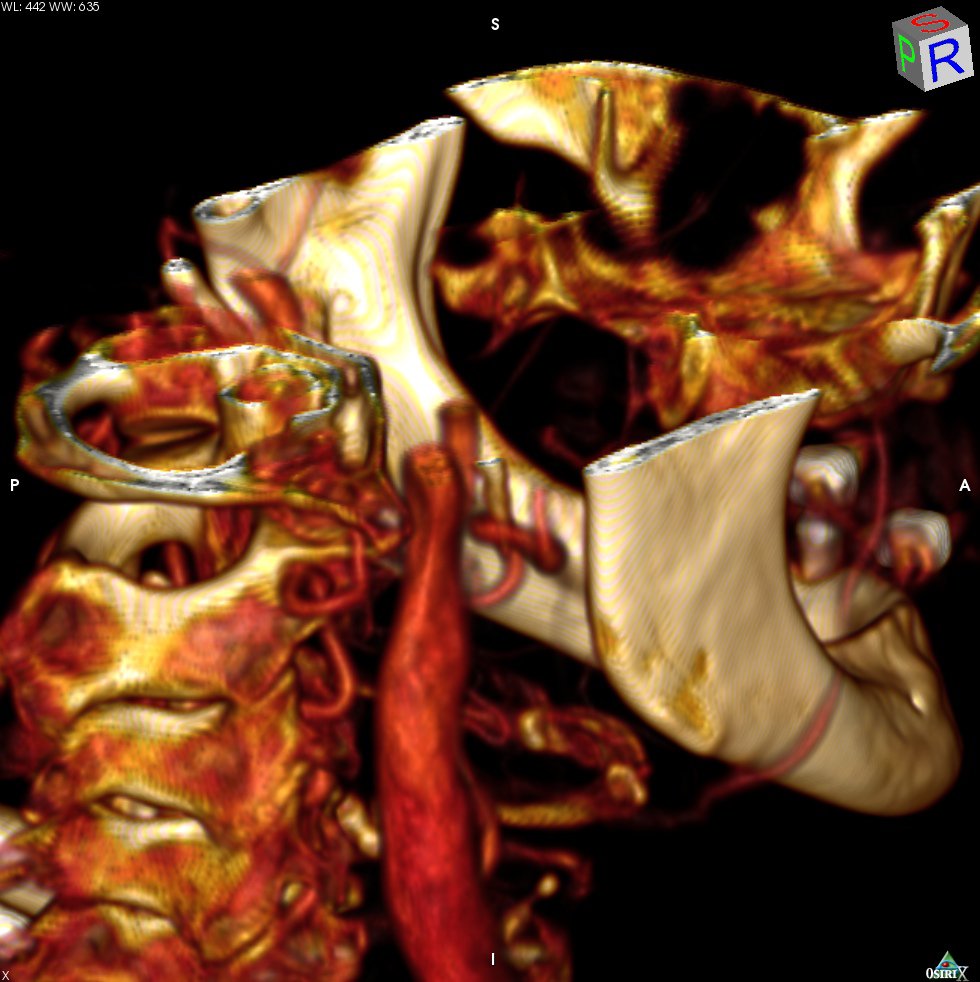

Pictures worth thousands of words.

MRI combined with image processing pipelines provide a powerful tool to inform doctors how to treat arrhythmias. Visualizations can help providers plan intervention and then to communicate findings and care plans to the patient.